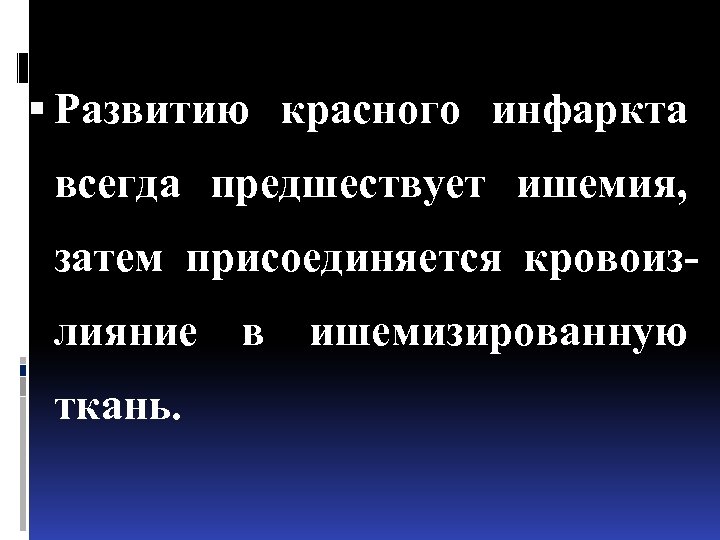

Развитию красного инфаркта всегда предшествует ишемия, затем присоединяется кровоизлияние в ишемизированную ткань.

Развитию красного инфаркта всегда предшествует ишемия, затем присоединяется кровоизлияние в ишемизированную ткань.